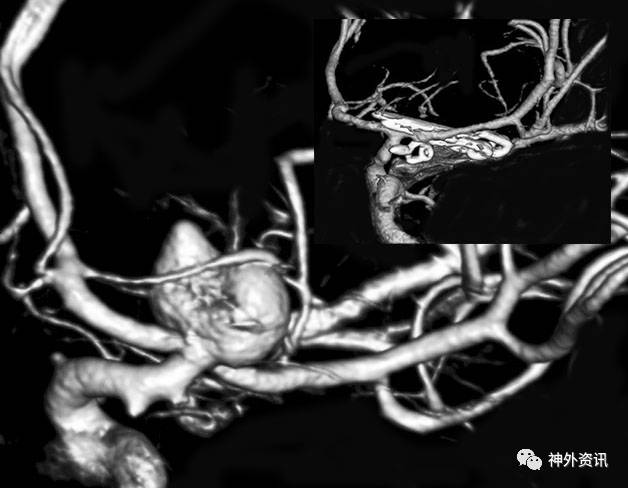

图1:一例典型的ICA分叉部动脉瘤,穿支血管绕着瘤顶走形。插图为术后CTA,可见术中使用了串联夹闭技术,同期夹闭一个小的脉络前动脉瘤。